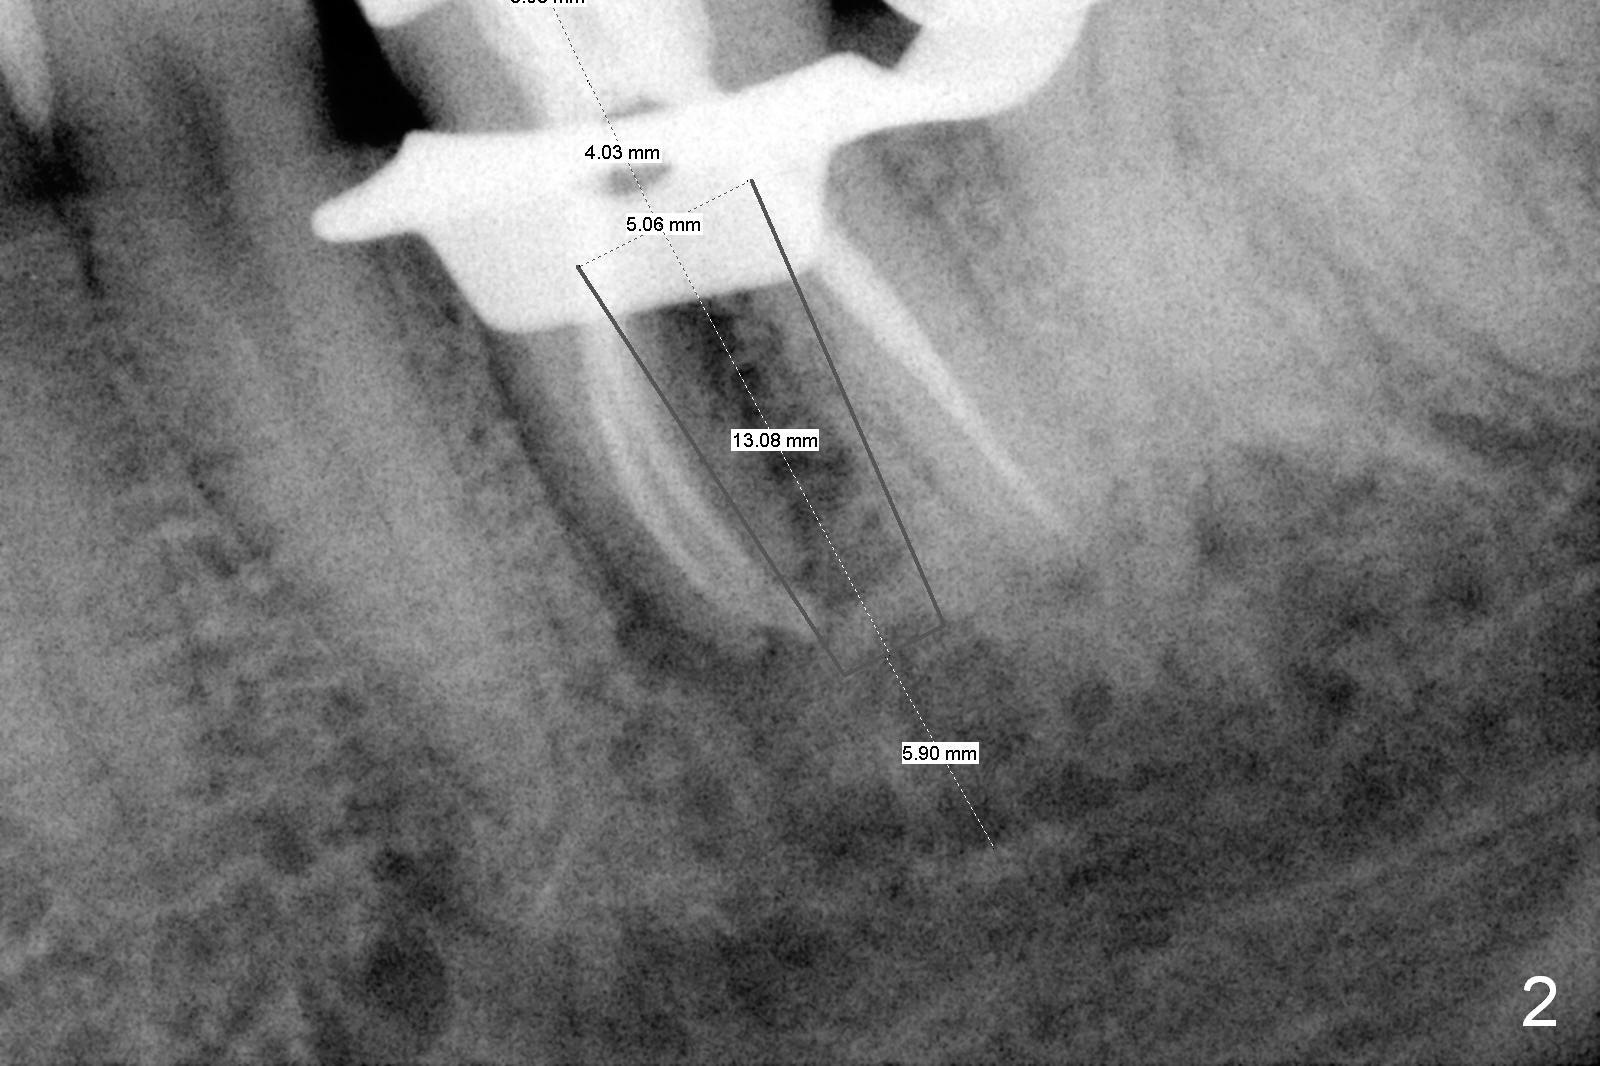

The tooth #19 is easy to get loose, but it cannot be luxated.  After sectioning and extraction (Clindamycin), the septum is found to be thin (Fig.4).  A surgical fissure bur is used to initiate osteotomy, followed by 1.6 mm pilot drill.  It is difficult to use Marking bur (wobbling over the basically pointed septum).  It is impossible to use 4.3 mm Magic Drill (MD, one drill system), since it jumps.  The smallest MD has to be used (2.8 mm).  When the next drill (3.3 mm) is being used for 13 mm with stopper (Fig.5), the patient experiences transient pain.  The depth is suggested from the design in Fig.2.  The thin septum appears not to be a reliable landmark.  When block anesthesia is administered, the initial depth should be shortened.  The drill appears to be close to the Inferior Alveolar Canal (Fig.5).  Then the depth changes to 11 mm with the following drills (3.8 and 4.3).  The mesial and distal walls of the septum are gradually perforated.  A 5x9 mm dummy implant is placed only after using 4.8 mm drill (Fig.6).  The implant appears to be short.  When a longer implant is placed (5x11 mm), it does not easily enter the osteotomy, either sliding into the mesial or distal socket with the implant separating from the implant driver.  It appears that a premount implant is appropriate in this situation.  When the 5x11 mm implant is finally seated with stability, it is 6 mm apical to the gingival margin.  The longest cuff of IBS abutment is 4 mm.  A longer implant is needed (Fig.7, 5x13 mm).  Placement is not easy as mentioned above.  Insertion torque is <20 Ncm when the patient experience a little discomfort.  A 6.5x4(4) mm pair abutment is placed (A), apparently proper for restoration.  Allograft is placed (Fig.8 *) prior to immediate provisional.  The patient complains of bad smell from the site 24 days postop.  When the provisional is removed, the abutment is found to be mobile.  When the latter is removed with local anesthesia, bone graft granules are attached to the socket above the lightly mobile implant (Fig.9).  In fact the latter appears to be stable after a few turns by finger.  A healing screw is placed; the socket is closed with collagen plug and 4-0 Chromic gut sutures (Fig.10).  It appears that a larger implant should have been used to achieve higher torque.  Two months later (3 months postop), the coronal end of the implant is partially exposed.  A 5x4 mm healing abutment is placed.  It appears that the implant is stable.  The implant appears to have osteointegrated 4 months postop (Fig.11).  Impression is taken.